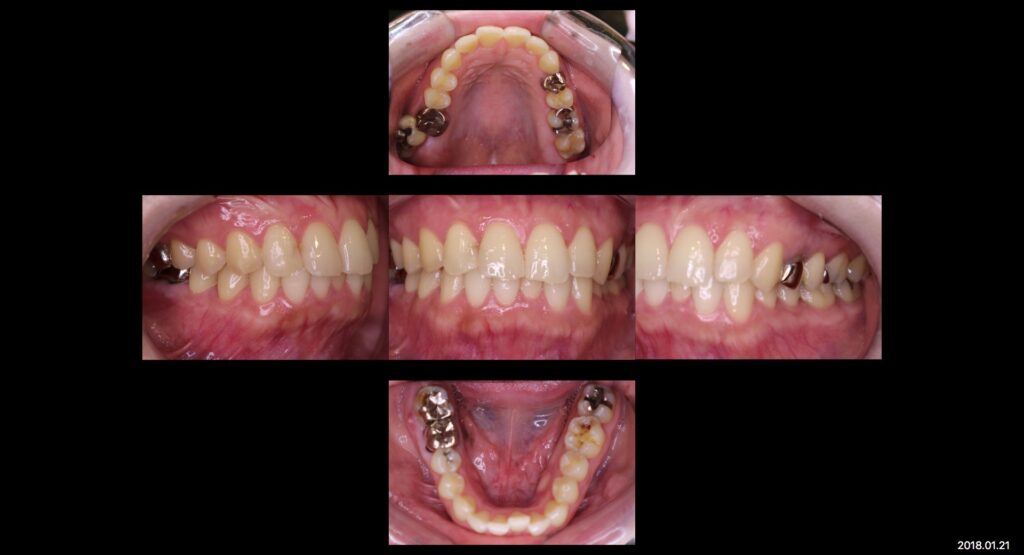

上:治療前口腔内写真

右上6、右下6、左上6,7、左下6→フルジルコニアCr

右上2→e-maxCr

左上5、左下7→e-maxIn

今回は補綴治療を終えた患者様の症例写真です✨

噛み合わせ、見た目を目的に補綴物のやりかえなど全顎的に根本治療を行いました。